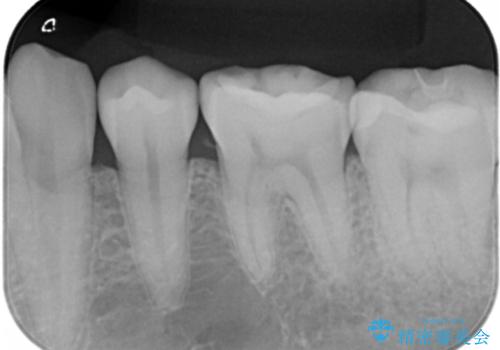

- 左下7番のCR劣化を自費治療にて希望された患者様です。

切削量を考慮してセラミックインレーでの治療を選択しました。

CR直下と隣接面にう蝕が進行していたので、除去した上で形成、印象しています。